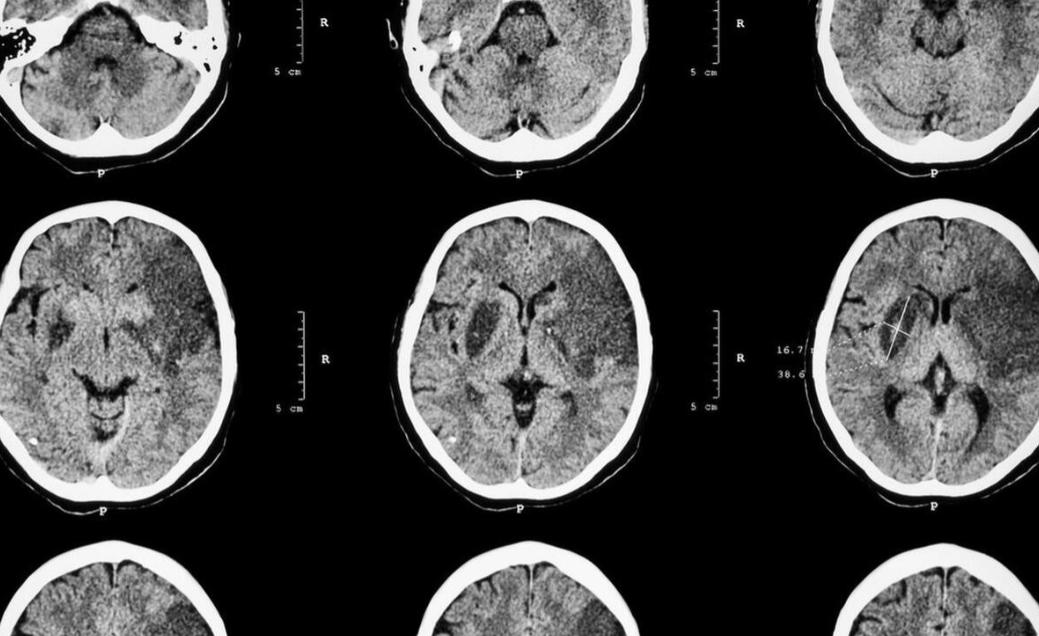

42岁男子脑梗死,从不喝酒抽烟,医生叹息:4件事做太多了

42岁,正值壮年,烟酒从来不沾,脑梗死这件事偏偏找上门来。这听起来让人觉得难以接受,却是真实存在的临床现象。